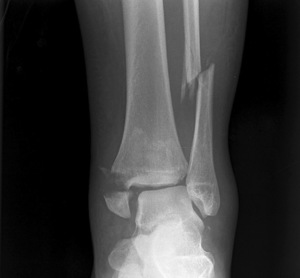

Переломы, трещины, смещения, — всему этому подвергается малая берцовая кость. Сегодня различается несколько видов переломов этой части, которые могут происходить в разных областях. Чаще всего перелом происходит в латеральной лодыжке. Лодыжка может повреждаться переломами тоже на разных уровнях. Очень часто они сочетаются с вывихом или подвывихом стопы, при этом происходит ее укорочение, а также разрыв межкостного дистального синдесмоза. Можно выделить следующие виды переломов:

Для того чтобы диагностировать перелом кости, важно внимательно рассмотреть симптомы. При переломе часто возникает отечность, может наблюдаться гематома. При пальпации поврежденной конечности пострадавший испытывает особо сильную боль. При визуальном осмотре кажется, что конечности человека имеют разную длину.

Перелом малоберцовой кости, как и другие переломы, начинает лечиться с восстановления прежнего положения костной части, в которой она находилась до травмы. Если травма не сопровождалась смещением, обычно накладывают гипсовую повязку сроком от четырех до шести недель. Гипс может накладываться до центра голени, все зависит от места повреждения. До середины бедра гипс накладывается при переломах головок малоберцовых костей или их шеек.